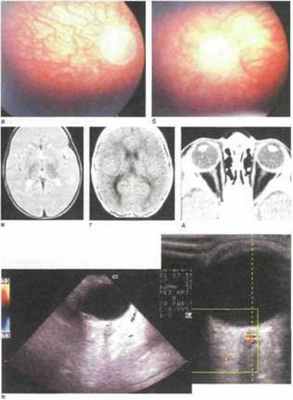

Рис. 13.12. Аплазия зрительного нерва. Диск зрительного нерва и центральные сосуды отсутствуют. Зоны депигментации и просвечивания хороидальной сосудистой сети [Blanco R. et al., 1992].

Рис. 13.13. Аплазия зрительного нерва. В заднем полюсе углубление и рудиментарный овальный диск, центральные сосуДы отсутствуют [Blanco R. et al., 1992].

• отсутствуют диск зрительного нерва, центральные сосуды и макулярная дифференциация (рис. 13.12) [Мосин И.М., Васильева О.Ю., 2004; Blanco R.

• визуализируется рудиментарный белый диск зрительного нерва, лишенный центральных сосудов; макулярные рефлексы не определяются (рис. 13.13);

• на месте диска зрительного нерва офтальмоскопируется глубокая полость, окруженная светлым кольцом, напоминающим перипапиллярный склеральный конус (рис.

13.14) ; центральные сосуды сетчатки отсутствуют [ Duke-Elder S., 19641.

13.14. Аплазия зрительного нерва. На месте диска зрительного нерва глубокая полость, центральные сосуды сетчатки и макулярная дифференциация отсутствуют [Blanco R et al., 1992].

• отсутствуют диск зрительного нерва, центральные сосуды и макулярная дифференциация (рис. 13.12);

• на месте диска зрительного нерва офтальмоскопируется глубокая полость, окруженная светлым кольцом, напоминающим пери папиллярный склеральный конус (рис.13.14); центральные сосуды сетчатки отсутствуют.

Офтальмологический статус. Острота зрения (по ЗВП) OU - 0- Девиация 0°. Пилообразный нистагм. Передний отрезок без патологии. Диаметр роговицы ОЭ и ОБ — 11 мм. Диаметр зрачка 4 мм, нет реакции зрачков на свет. При офтальмоскопии обнаружено отсутствие диска зрительного нерва и центральных сосудов сетчатки (рис. 13.15, а, б). Сетчатка слабо пигментирована, определялась только хороидальная сосудистая сеть, область макулы не дифференцировалась.

Переднезадняя ось каждого из глаз при эхобиометрии составляла 19,2 мм.

ЭРГ субнормальная — амплитуда Ь-волны снижена на 20 % по сравнению с возрастной нормой. При записи ЗВП на стимуляцию вспышкой и реверсивными паттернами размерами 220—16' ответные реакции не регистрировались.

Обнаружена рудиментарная твердая мозговая оболочка, входящая в склеру в нормальной позиции (рис. 13.15, д). Плотность образованного твердой мозговой оболочкой стебля в интраорбитальном отделе варьировала от +16 до +18 ед X (в норме плотность зрительного нерва составляет + 22- + 28 ед.Х).

При цветовом допплеровском картировании орбиты сосудов в границах интраорбитального отрезка рудиментарного «зрительного нерва» не обнаружено (рис. 13.15, е). Акустические вызванные потенциалы в пределах возрастной нормы.

Нейрорадиологические исслелования. При ультразвуковом исследовании, КТ и МРТ орбит могут определяться рудиментарная твердая мозговая оболочка зрительного нерва (см. рис. 13.15, д, е), уменьшение размеров глазного яблока и орбит. При НСГ, КТ или МРТ головного мозга у пациентов с аплазией зрительного нерва часто выявляют гидранэнцефалию, анэнцефалию, орбитальное менингоэнцефалоцеле, признаки септооптической дисплазии. При MPT у пациентов с аплазией зрительного нерва обычно определяется гипоплазия хиазмы.